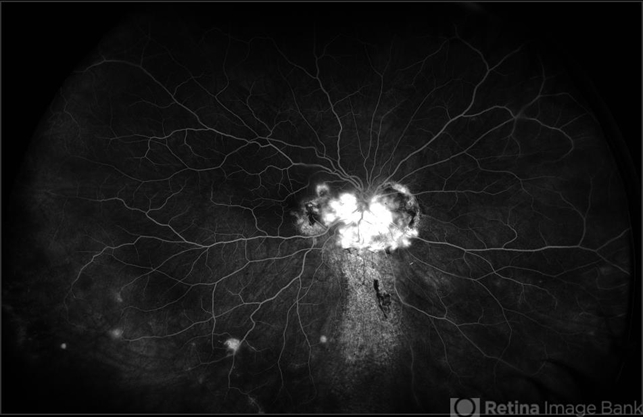

- ultra-wide field imaging, fluorescein leakage, Optos, Von Hippel-Lindau, retinal hemangioblastoma, optic disc, fluorescein angiogram (FA)

- Ultra-wide-field fluorescein angiogram of the right eye of an 29-year-old female with an optic nerve hemangioblastoma secondary to Von Hippel-Lindau Syndrome.